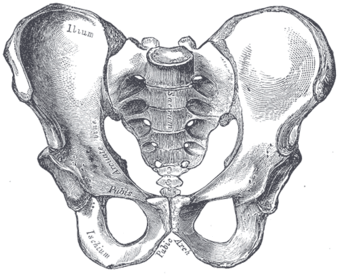

صورة لحوض ذكر (العجز في الوسط) | |

في البشر، العجز sacrum ( []ˈsækrəm[] أو []ˈseɪkrəm[]; مفرده: sacrums أو sacra)، هي عظام كبيرة، مثلثة الشكل، تقع على قاعدة العمود الفقري وعلى الجزء العلوي، الخلفي لتجويف الحوض، حيث تكون مغروزة مثل الوتد بين عظام الورك. الجزء العلوي منها تتصل بالفقرة القطنية، والجزء السفلي منها متصلة بالعصعص. عادة، يبدأ العجز كفقرة خامسة غير ملتحمة تبدأ بالالتحام في عمر 16-18 سنة وعادة ما يكتمل التحامها كعظمة واحدة في الرابعة والثلاثين.